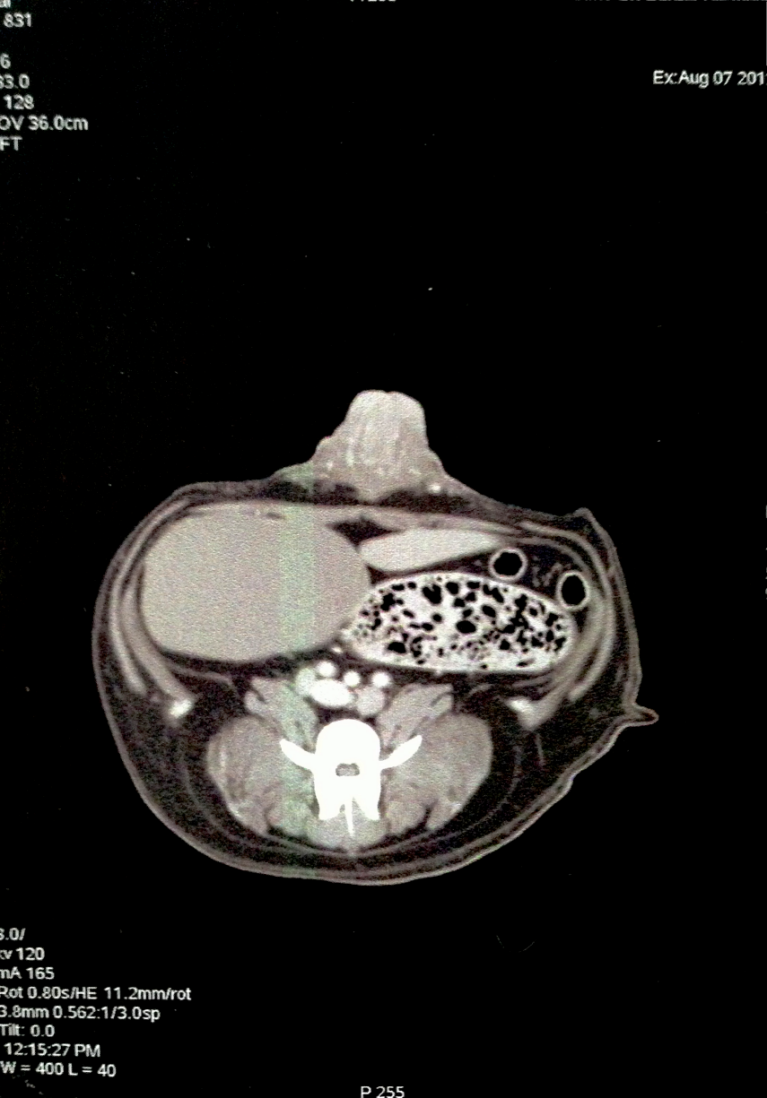

Les scanners abdominaux:

Le scanner n'est pas l'examen le plus utilisé en médecine vétérinaire pour explorer un abdomen: son prix est prohibitif alors que l'échographie, moins honereuse, apporte déjà beaucoup d'information ...

Scanner normal d'abdomen

Scanner normal d'abdomen: produit de contraste au niveau de la veine porte pour une recherche de shunt

SCANNER ABDOMINAL INTEGRAL